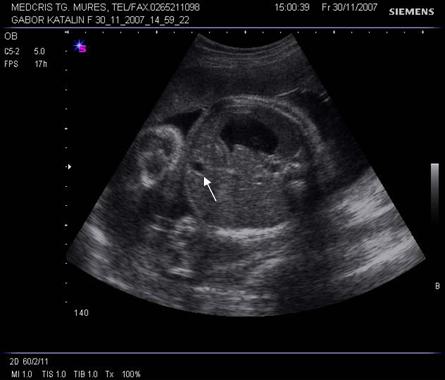

Fig. nr.177. Planul 1 de sectiune, cu imaginea de inima in 4 camere.